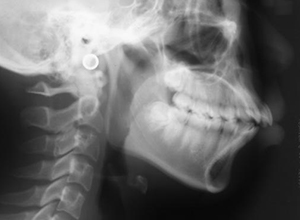

X-Ray

X-Ray所見

セファロ所見 Sellaから下顎頭までの距離は短い。下顎枝、骨体部共に大きく下顎角はそれほど大きくはない。頭蓋底の前後的距離は短くなく、中顔面の奥行きもあるが、NasionからA点までの垂直的距離があるため、下顎はクロックワイズローテーションをしておりⅡ級傾向が認められた。上下顎前歯は唇側傾斜を呈していた。